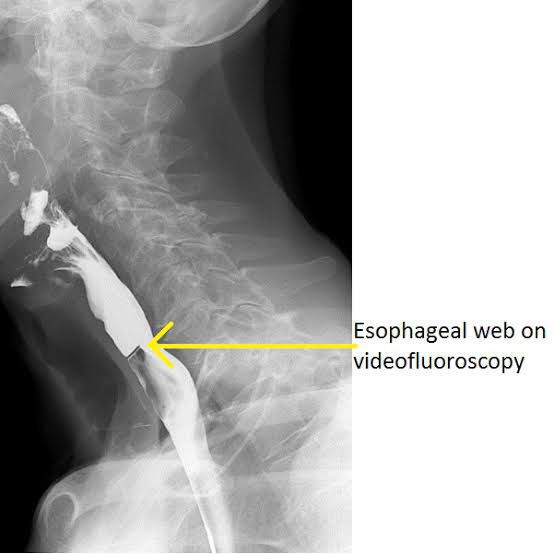

A disorder marked by anemia caused by iron deficiency, and a web-like growth of membranes in the throat that makes swallowing difficult. Having Plummer-Vinson syndrome may increase the risk of developing esophageal cancer. Also called Paterson-Kelly syndrome and sideropenic dysphagia. Plummer-Vinson syndrome classically presents as a triad of iron-deficiency anemia, postcricoid dysphagia, and upper esophageal webs. [2] Long-standing iron deficiency anemia can present as dyspnea or difficulty breathing, tachycardia, weakness, pallor, and koilonychia or spoon nails. The cause of Plummer-Vinson syndrome is unknown. Genetic factors and a lack of certain nutrients (nutritional deficiencies) may play a role. It is a rare disorder that can be linked to cancers of the esophagus and throat. It is more common in women